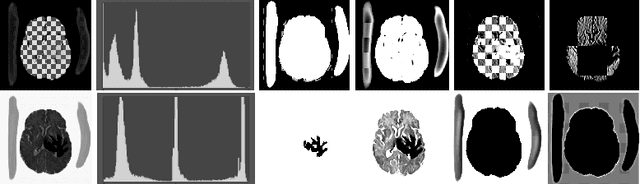

We introduce a neural network framework, utilizing adversarial learning to partition an image into two cuts, with one cut falling into a reference distribution provided by the user. This concept tackles the task of unsupervised anomaly segmentation, which has attracted increasing attention in recent years due to their broad applications in tasks with unlabelled data. This Adversarial-based Selective Cutting network (ASC-Net) bridges the two domains of cluster-based deep learning methods and adversarial-based anomaly/novelty detection algorithms. We evaluate this unsupervised learning model on BraTS brain tumor segmentation, LiTS liver lesion segmentation, and MS-SEG2015 segmentation tasks. Compared to existing methods like the AnoGAN family, our model demonstrates tremendous performance gains in unsupervised anomaly segmentation tasks. Although there is still room to further improve performance compared to supervised learning algorithms, the promising experimental results shed light on building an unsupervised learning algorithm using user-defined knowledge.